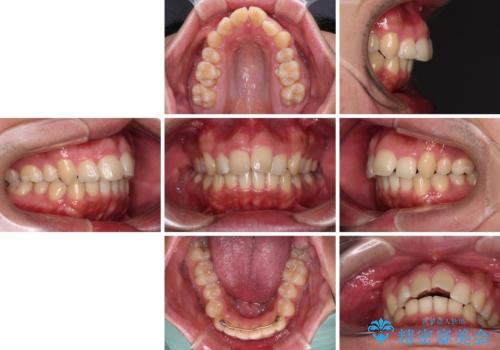

- 学生時代に抜歯矯正した歯列が後戻りしてきたとのことで来院された患者様です。

舌の突出癖が原因で上顎前歯が前方に移動したと考えられたため、舌のトレーニングを徹底して行っていただきながら、後戻りを解消していくこととしました。

マウスピース矯正でもワイヤー矯正でも対応可能でしたが、患者様の希望によりワイヤー装置による矯正治療を行うこととしました。

上顎歯列全体がスムーズに後方移動でき、1年で治療を終えることができました。